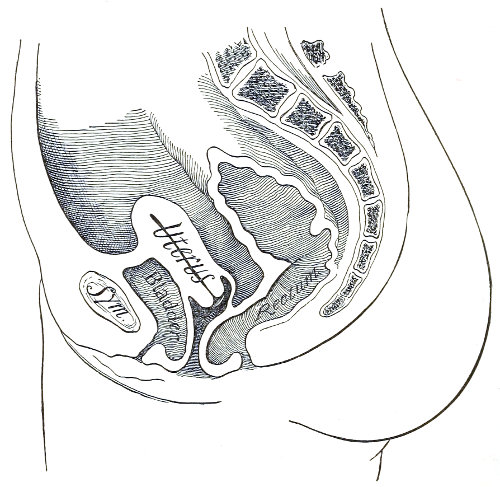

Vaginal and Bimanual Examination.—Having examined and noted the condition of the external genitals, the physician should next proceed to examine the vagina. The index finger of the right or the left hand should be gently introduced into the vagina. The condition of the vaginal walls, and the direction, consistency, form, etc. of the vaginal cervix, may be determined. The shape and size of the os uteri should be noted. The ulnar edge and the tips of the fingers of the other hand should then be placed upon the abdomen, immediately above the symphysis pubis, and gently pressed backward and downward toward the vaginal finger 24 (Fig. 2). In this way the various pelvic organs, the uterus, Fallopian tubes, ovaries, and ureters, may be palpated between the two hands, and their position, size, shape, and consistency may be determined. Such an examination is, of course, made much more easily in a thin woman than in a fat one. A thin woman a few weeks after labor may be examined most easily, on account of the relaxation of the abdominal and vaginal walls.

Fig. 2.—Bimanual examination.

In making the bimanual examination the structures 25 should be palpated methodically in order. The vaginal finger notes the condition of the cervix uteri. If the fundus be in the normal position, the uterus can then be taken between the abdominal hand (upon the fundus) and the vaginal finger (upon the cervix) (Fig. 3). The shape, size, mobility, and consistency are noted. The vaginal finger is then passed anteriorly and laterally toward either uterine cornu, while the abdominal fingers pass over to the posterior aspect of the same cornu. The ovarian ligament and the proximal end of the Fallopian tube may thus be felt. Passing farther outward, the whole of the tube and the ovary may be examined. The same procedure is then applied to the opposite side.

Fig. 3.—Bimanual examination; median sagittal section of the pelvis.